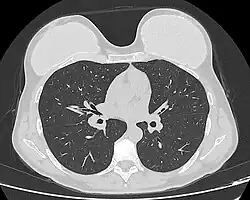

Silicone implant rupture can be evaluated using magnetic resonance imaging; from the long-term MRI data for single-lumen breast implants, the European literature about second generation silicone-gel breast implants (1970s design), reported silent device-rupture rates of 8–15 per cent at 10-years post-implantation (15–30% of the patients).[51][52][53][54] Additionally, high-resolution ultrasound is another effective method of evaluating silicone implant integrity.[55]

The study Safety and Effectiveness of Mentor's MemoryGel Implants at 6 Years (2009), which was a branch study of the U.S. FDA's core clinical trials for primary breast augmentation surgery patients, reported low device-rupture rates of 1.1 per cent at 6-years post-implantation.[56] The first series of MRI evaluations of the silicone breast implants with thick filler-gel reported a device-rupture rate of 1 percent, or less, at the median 6-year device-age.[57] Statistically, the manual examination (palpation) of the woman is inadequate for accurately evaluating if a breast implant has ruptured. The study, The Diagnosis of Silicone Breast implant Rupture: Clinical Findings Compared with Findings at Magnetic Resonance Imaging (2005), reported that, in asymptomatic patients, only 30 per cent of the ruptured breast implants are accurately palpated and detected by an experienced plastic surgeon, whereas MRI examinations accurately detected 86 per cent of breast implant ruptures.[58] Therefore, the U.S. FDA recommended scheduled MRI examinations, as silent-rupture screenings, beginning at the 3-year-mark post-implantation, and then every two years, thereafter.[24] Nonetheless, beyond the U.S., the medical establishments of other nations have not endorsed routine MRI screening, and, in its stead, proposed that such a radiologic examination be reserved for two purposes: (i) for the woman with a suspected breast implant rupture; and (ii) for the confirmation of mammographic and ultrasonic studies that indicate the presence of a ruptured breast implant.[59]

Furthermore, The Effect of Study design Biases on the Diagnostic Accuracy of Magnetic Resonance Imaging for Detecting Silicone Breast Implant Ruptures: a Meta-analysis (2011) reported that the breast-screening MRIs of asymptomatic women might overestimate the incidence of breast implant rupture.[60] In the event, the U.S. Food and Drug Administration emphasised that "breast implants are not lifetime devices. The longer a woman has silicone gel-filled breast implants, the more likely she is to experience complications."[61]